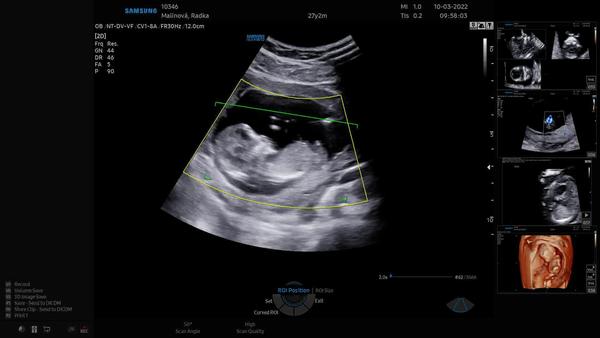

včera jsme byli na 1. screeningu a na pracovišti, kde jsme byli, říkají pohlaví až od 16. tt. Jsme objednaní na izo období na ultrazvuk, ale vím, že jinde říkají pohlaví i dříve. Nevíte, prosím, dle fotek, co čekáme?

Gestační věk miminka je 13+4.